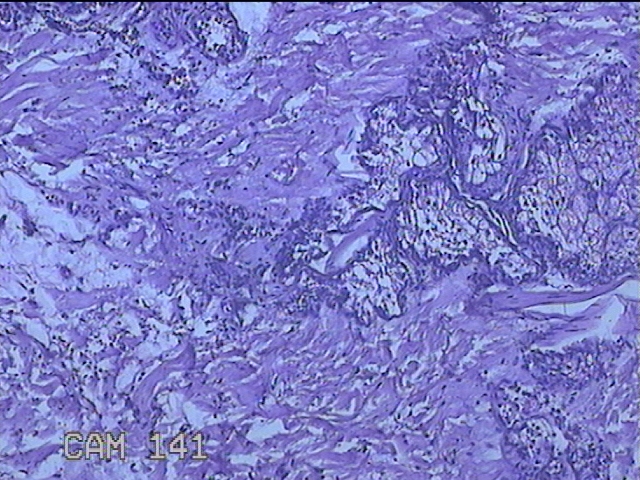

左侧额部结节

性别

男

年龄

29岁

临床诊断

皮脂腺囊肿

一般病史

发现左额部结节1周余。

标本名称

大体所见

灰白粉红色带皮肤样结节1x0.8x0.7cm一个,表面光滑,切开结节呈实性,切面灰白粉红色,质软。